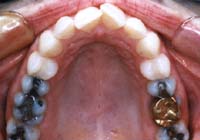

Treatment Time: 6 months

Aligners: 12 Upper, 7 Lower